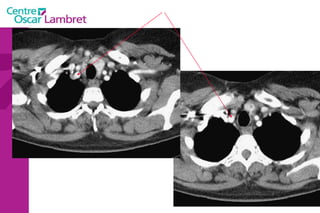

Les  3 troncs supra aortiques  naissent sur la portion horizontale de la crosse de l’aorte : Le tronc Artériel Brachio-céphalique. L’artère Carotide commune gauche. L’artère sus-clavière gauche. Tous ont une branche à destinée céphalique. L’appareil circulatoire

Les 3troncs supra aortiques naissent sur la portion horizontale de la crosse de l’aorte : Le tronc Artériel Brachio-céphalique. L’artère Carotide commune gauche. L’artère sus-clavière gauche. Tous ont une branche à destinée céphalique. L’appareil circulatoire

Les Troncs Supra Aortiques s’organisent autour de la trachée à leur origine. L’appareil circulatoire

Les Troncs SupraAortiques s’organisent autour de la trachée à leur origine. L’appareil circulatoire